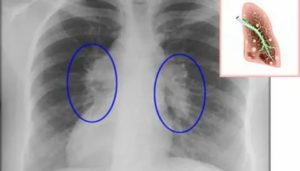

- Рентген. Проводится рентгенография в нескольких проекциях. Метод позволяет определить область поражения и характер процесса. На снимках патология проявляется затемнениями с размытыми контурами (на фото).

Плеврит легких на рентгенограмме